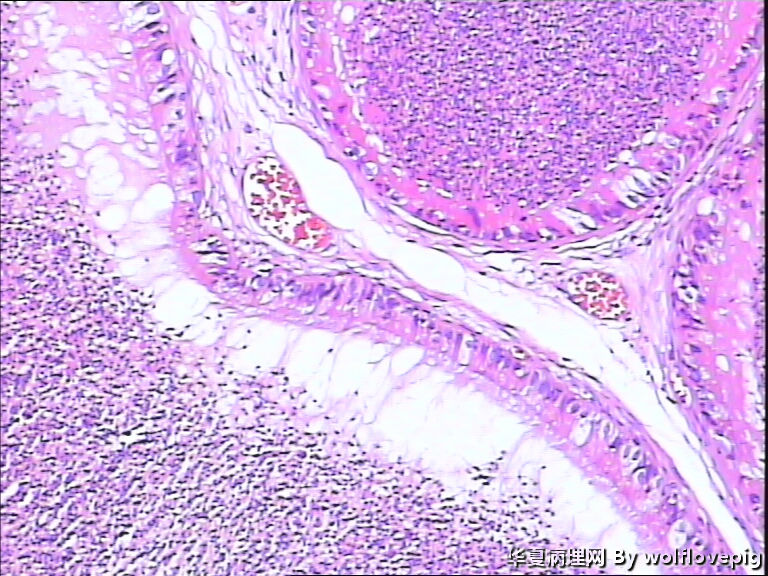

62y,双侧附睾。

送检附睾管囊性扩张,管腔结构较完整,多数管腔内见精子积聚,少数管腔内有出血。

符合精子肉芽肿。

取材切片附睾管扩张,精子淤积,部分区域出血

未见肉芽肿结构,也未见其它异常。

有出血,腔内大量精子,未见特异病变